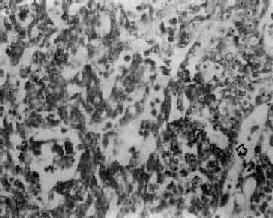

鼻咽泡状核细胞癌

图9-6 鼻咽泡状核细胞癌

癌细胞境界不清,呈合体状,核大圆形,染色质少,呈空泡状,含1~2个肥大的核仁,癌细胞间有淋巴细胞浸润